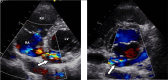

Figure 1.

Figure 1.. A 35-year-old woman with recurrent attacks of palpitation since childhood. A) Transthoracic color Doppler echocardiography shows the dilated left circumflex artery (arrow) emptying into the big coronary sinus. B) Continuous turbulence flow on color Doppler at the level of coronary artery-coronary sinus connection as well as in the coronary sinus indicating a left-to-right shunts flow.